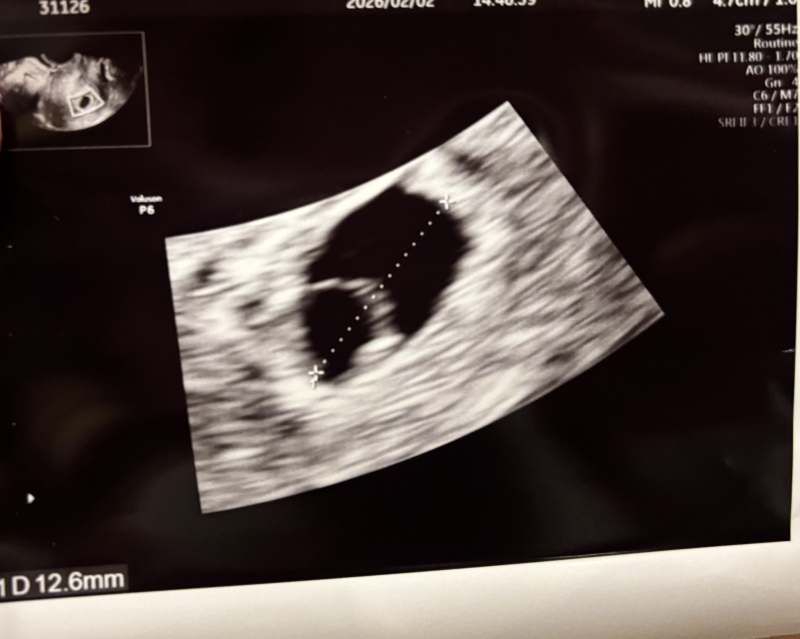

前々回5w6dで検診行ったところ、胎嚢、卵黄嚢が確認でき10.2mmでした。

前回 6w6dで診察に行った際に、「これが心拍かなーどうかなー、、、来週またみてみましょう。胎嚢が自身で思っている週数だと小さめかな」って言われました。ちなみに胎嚢が12.6mmでした。